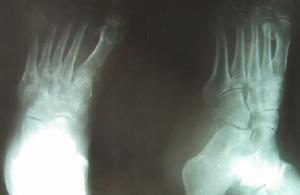

感染性關節炎人咬後關節感染多是無痛性,一周后症狀出現,貓和狗咬後會在24小時內出現手部關節的紅,腫,痛,鼠咬後還會有發熱,皮疹,關節痛及局部淋巴結病(2~10天的潛伏期)。

感染性關節炎被人咬傷後引起的關節感染多由革蘭氏陰性菌如B型鏈球菌,口腔厭氧菌(如梭狀芽胞桿菌,鏈球菌,類桿菌)引起.動物咬傷後引起的關節感染常為金黃色葡萄球菌或口腔菌叢.在狗和貓咬後巴斯德菌感染占1/2.狗和貓咬後還可引起假單胞菌屬,摩拉克菌屬及噬血桿菌屬感染.鼠咬後可引起擬放線鏈桿菌或小螺菌感染。